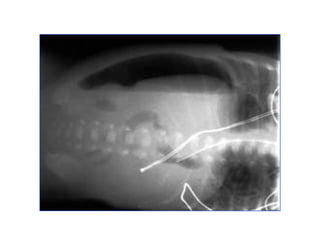

Crohn ruột non – túi thừa ruột non

Crohn ruột non– túi thừa ruột non